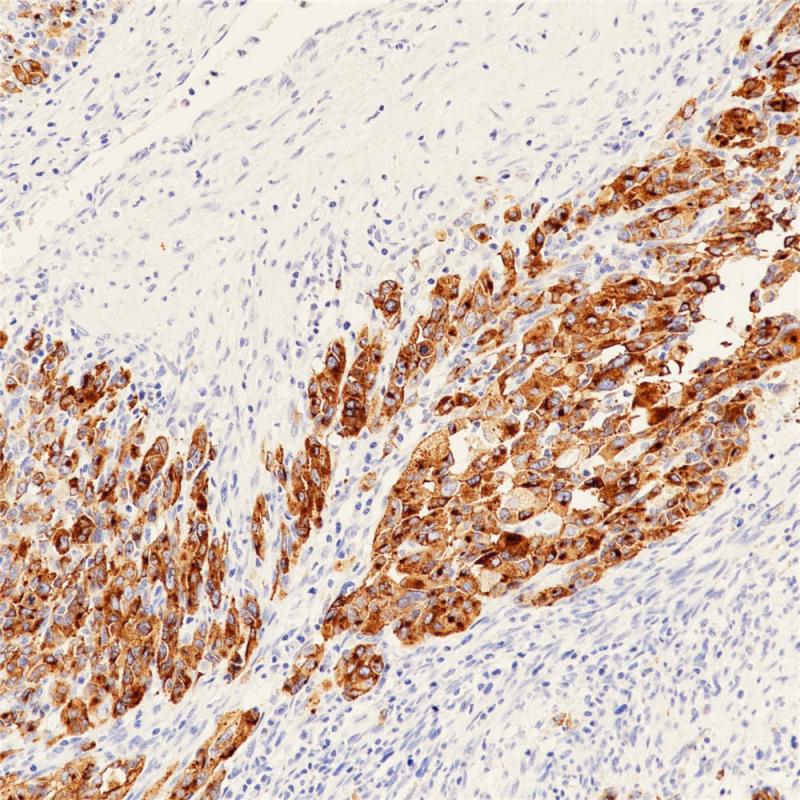

垂体前叶Growth Hormone(BPM6190)染色

生长激素(GH),促生长激素,是负责调节全身生长的主要激素,在有机代谢中也很重要。它是由垂体前叶的嗜酸性或促生长细胞合成的。生长激素通过促进肝脏产生体细胞素间接刺激生长,而体细胞素直接作用于骨骼和软组织导致生长。生长激素对肝脏、脂肪组织和肌肉产生直接的代谢影响。一般来说,生长激素促进蛋白质合成,保存碳水化合物,消耗脂肪储存。

推荐使用人类生长激素(HGH)检测正常和肿瘤组织中感兴趣的特异性抗原,作为常规组织病理学的辅助手段。

阳性对照

脑垂体

亚细胞定位

细胞质